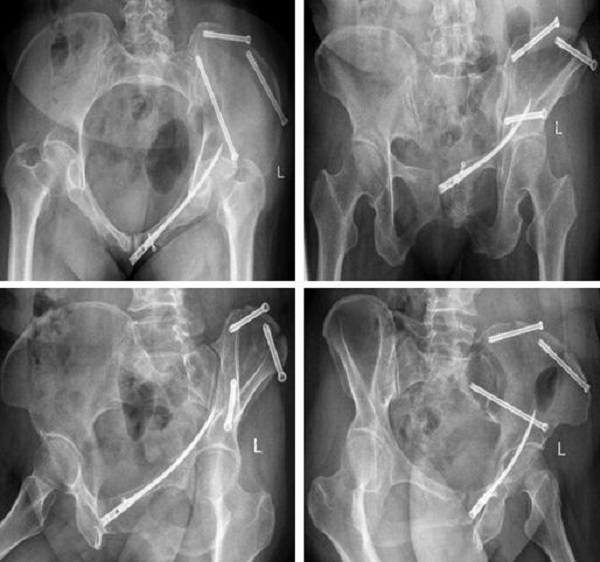

术前,创伤骨科郭永良主任医师团队应用MIMICS软件重建患者骨盆LC-II通道螺钉方向和长度,术中郭永良主任亲自主刀,使用Schanz针协助闭合复位,结合术前模拟通道螺钉方向精确制导,以最小的创伤将LC-II通道螺钉顺利置入合适位置,而且完美避开神经及血管损伤,仅通过3枚螺钉使骨盆LC-II型骨折得到有效的稳定固定。

术后复查: